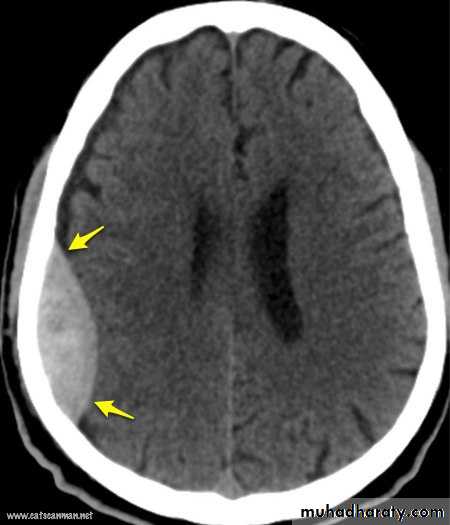

The bone of calvarium is thinnest in the temporal fossa. Strong blows to the side head may cause a depressed fracture, in which a fragment of bone is depressed inward to compress or injure the brain. At the pterion , the middle meningeal artery is easily ruptured following such an injury CAUSING EXTRA DURAL HEMATOMA that compress the brain and could be fatal if untreated.Benign masseteric hypertrophy is a relatively uncommon condition that can occur unilaterally or bilaterally . pain may be a symptom, but most frequently a clinician is consulted for cosmetic reasons . although it is tempting to point to malocclusion, bruxism , clenching or based on awareness of the condition, clinical and radiographic finding, and exclusion of more serious pathology such as benign and malignant parotid disease